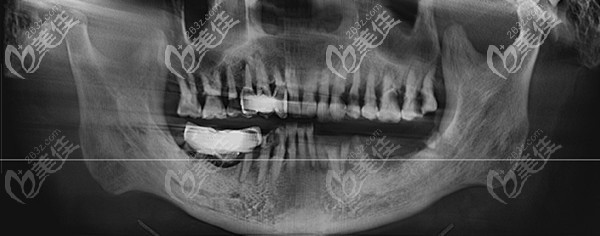

之前許多人不注腔健康,會導(dǎo)致牙齒缺失的情況。然而時間越來越久,發(fā)現(xiàn)缺失的牙不僅影響吃東西,還不美觀。那要是已經(jīng)過了8年多,還能再做韓國奧齒泰種植牙嗎?

牙齒疾病或者是外在因素,都會導(dǎo)致牙齒缺失,那就需要做種植牙才能改善。一直聽說石家莊趙翠彩做即刻負重修復(fù)效果不錯,價格還不貴,來看下真實案例就知道。